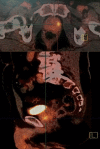

Case presentation: We report a Caucasian case of a mixed prostatic carcinoma, with the largest component being the large-cell neuroendocine carcinoma, in a patient who underwent a total prostatectomy for a localized cancer. Diagnostic, histological, therapeutic and evolutive aspects are reported and discussed.